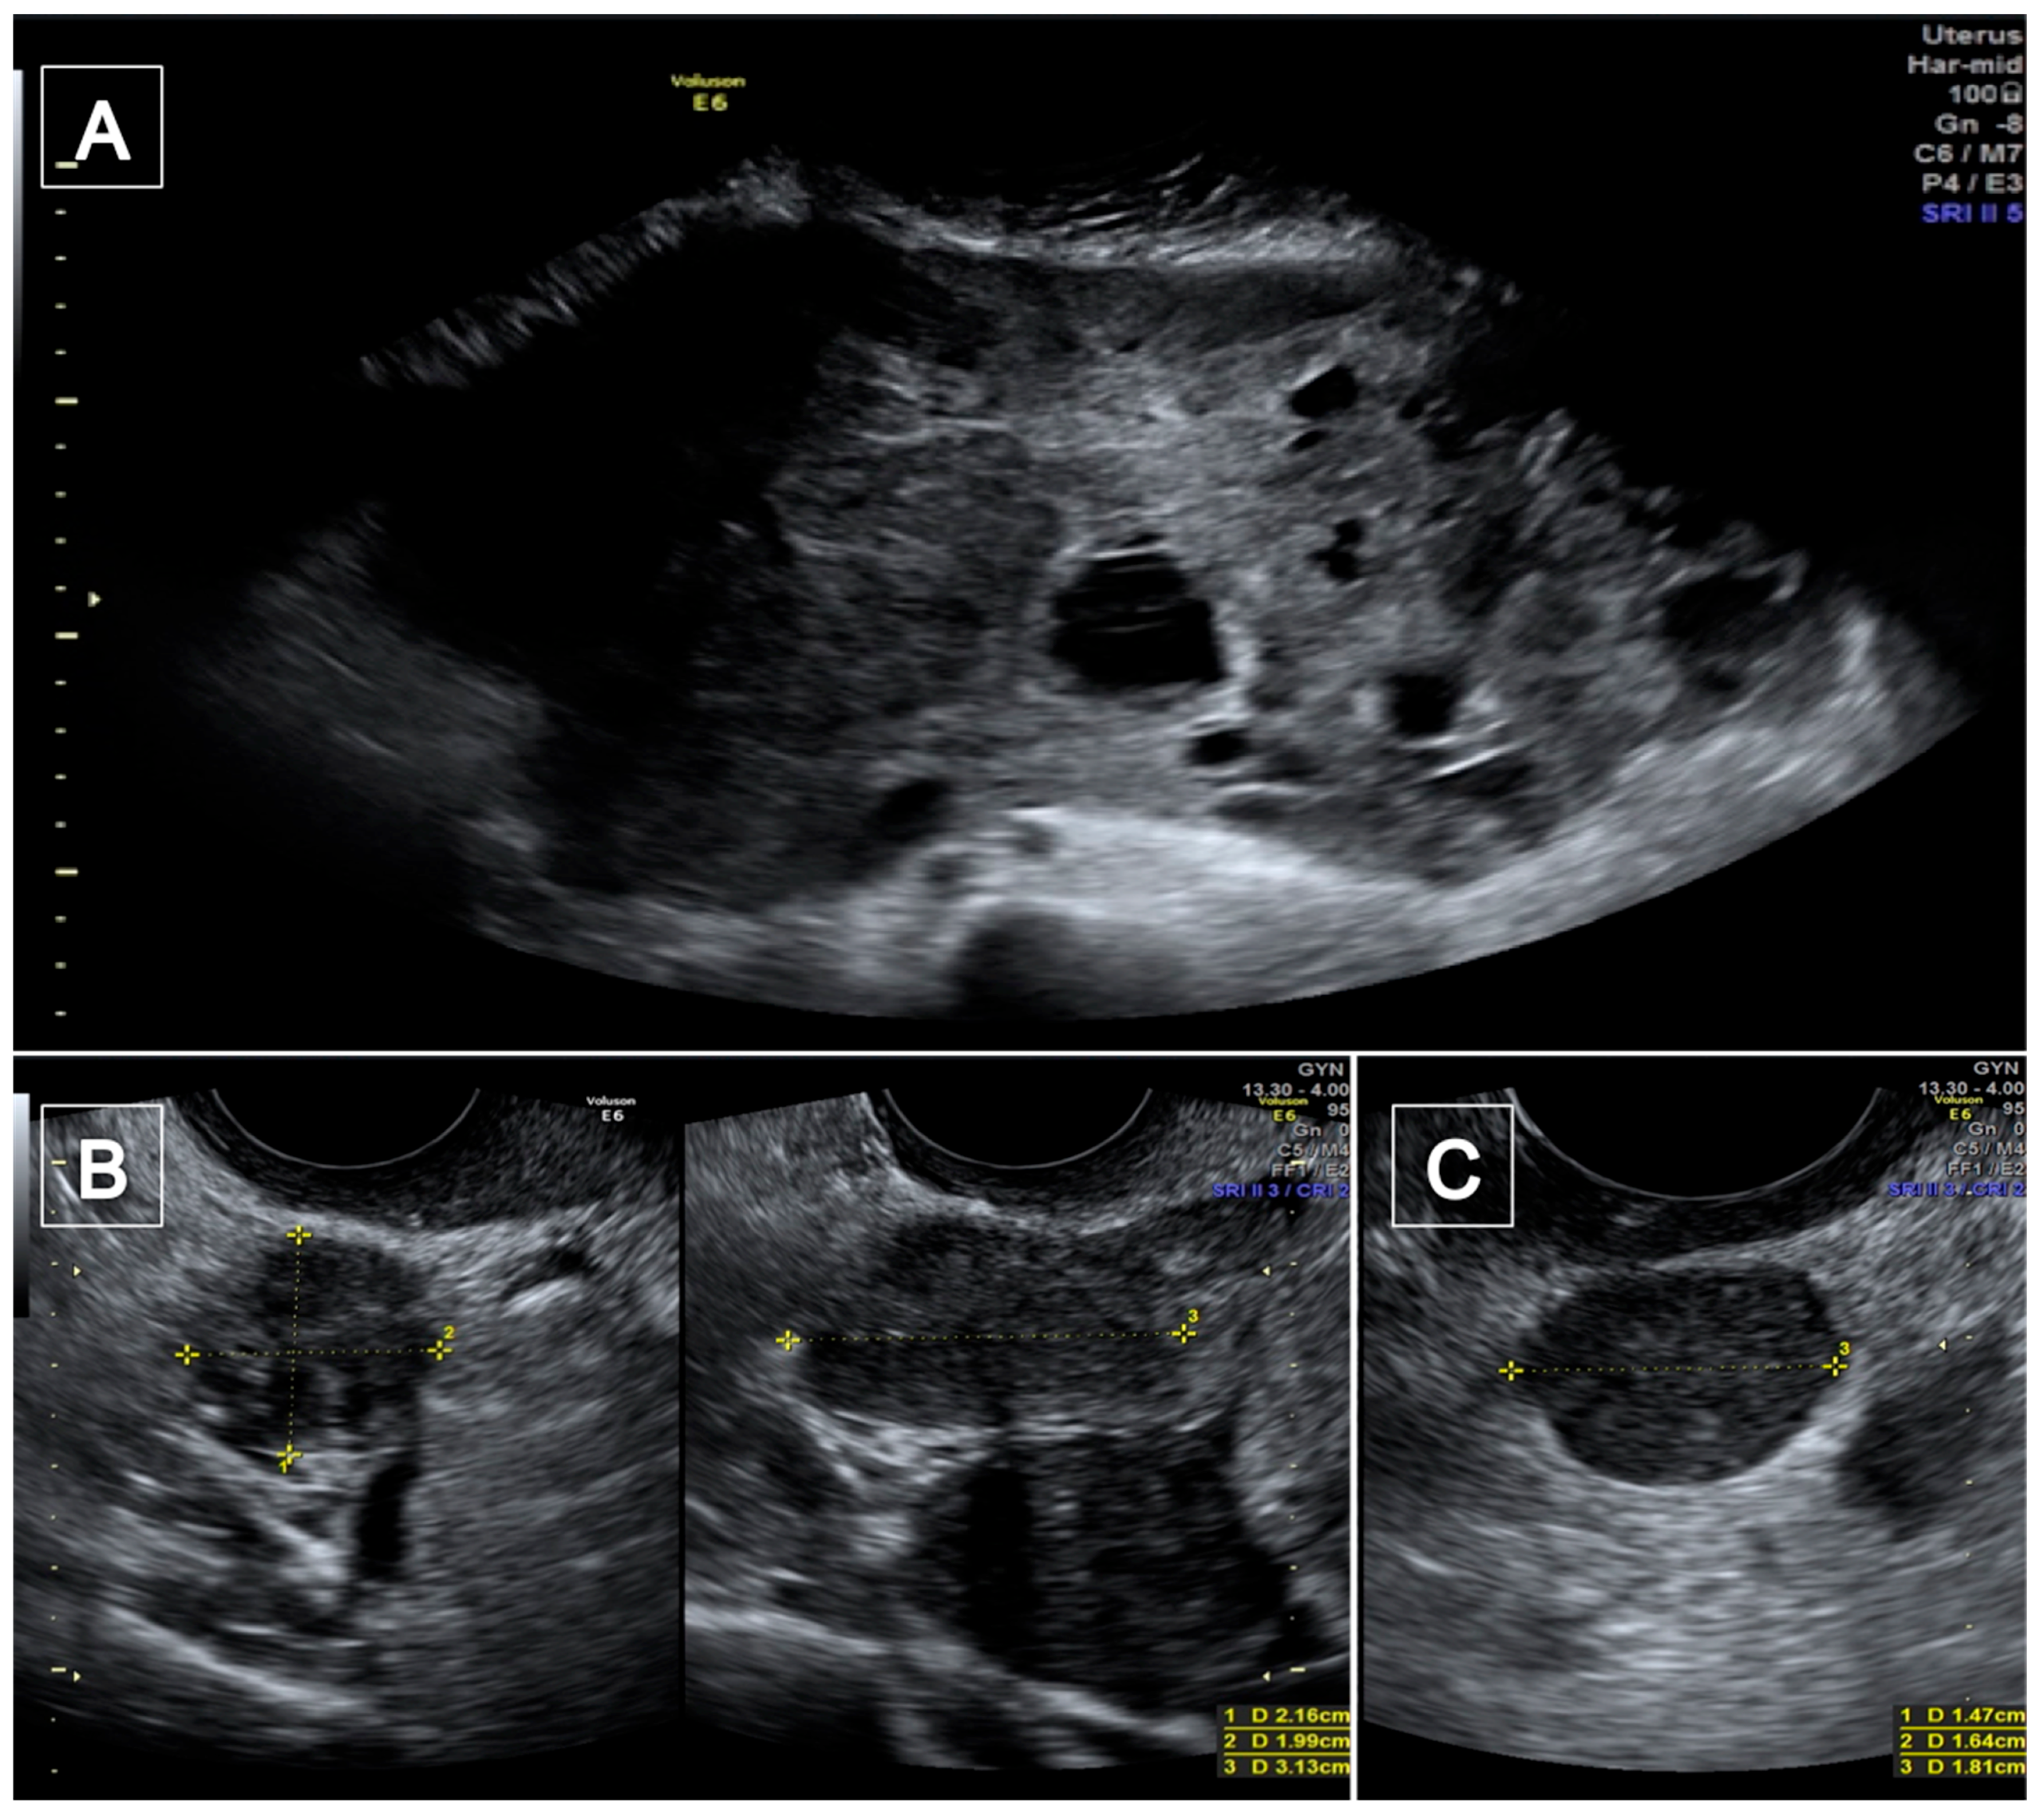

| Vimercati et al. 2022 * | 47 | 6 | Pelvis | High-grade Leiomyosarcoma with two omental metastases | TV ultrasound CT scan | Yes |